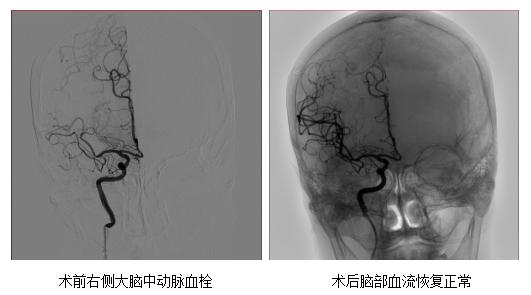

其结果显示一侧的大脑中动脉闭塞。

卒中团队仅用了20分钟左右就完整取出血栓,

患者的脑部血流恢复正常。

取出0.6mm的血栓